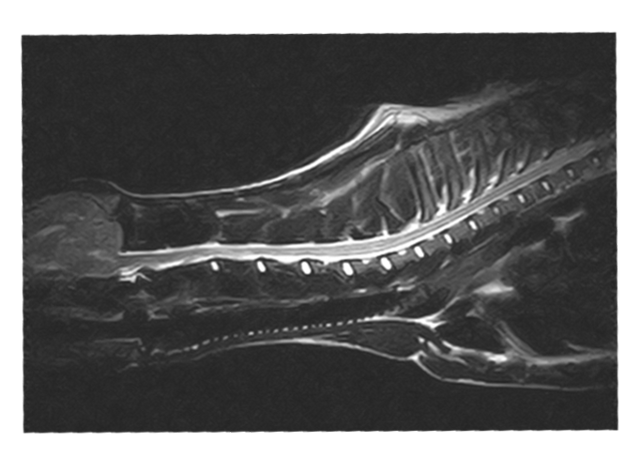

W obrębie kanału kręgowego najczęstszymi wskazaniami do badania rezonansem magnetycznym u zwierząt są:

• ocena przepukliny i stopnia ucisku na rdzeń kręgowy

• dyskopatie, neuropatie, radikulopatie

• urazy kręgosłupa

• zwyrodnieniowe zwężenie lędźwiowe krzyżowe (DLSS)

• spondylomielopatia szyjna